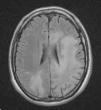

Se efectuó resonancia magnética por imágenes (RMI) con contraste en la que se observó extensa lesión subcortical en lóbulo frontal, parietal y occipital izquierdos, con extensión al esplenio del cuerpo calloso y mesencéfalo superior del lado izquierdo, y compromiso de los lóbulos parietal y occipital derechos. Las imágenes predominaban en lóbulos posteriores y dibujaban las fibras subcorticales en «U». No hubo realce con el contraste IV, ni efecto de masa sobre estructuras adyacentes de la línea media (figs. 1-5).

El VJC se reactiva ante cuadros de inmunosupresión grave, e induce la infección lítica de los oligodendrocitos con lesiones multifocales de desmielinización. La enfermedad tiene una prevalencia del 1 al 4% entre los pacientes con sida. El curso clínico es progresivo y con déficit neurológico focal en el 80% de los pacientes afectados. El examen del LCR es normal o con alteraciones inespecíficas, (hiperproteinorraquia moderada y pleocitorraquia mononuclear)4. La RM muestra la presencia de lesiones, por lo general bilaterales, simétricas o asimétricas, con predominio en lóbulos parieto-occipitales, bien delimitadas y localizadas en áreas periventriculares y en la sustancia blanca subcortical. Pueden ser únicas o múltiples, no refuerzan con el contraste, no están rodeadas de edema, ni producen efecto de masa, y dibujan las fibras subcorticales en «U» o fibras arcuatas; un tercio de los pacientes tienen compromiso de la fosa posterior. Entre un 5-10% de los casos, esta última localización se revela como la única manifestación de la enfermedad4. El diagnóstico se confirma por la PCR en el LCR. La sensibilidad de la prueba es variable (40-80%), posee una alta especificidad (mayor del 90%) y un valor predictivo positivo del 100%5.